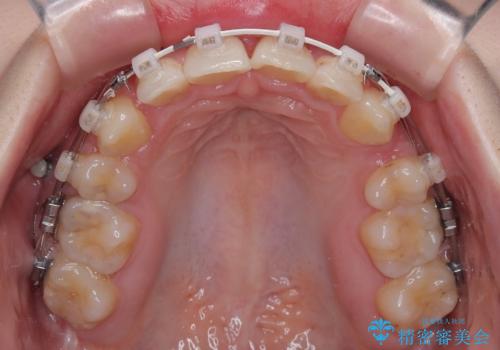

- 審美装置

- デコボコになっている前歯を気にして来院された患者様です。

口元の突出感は気になっていないものの、デコボコを解消すると口元が前方に突出する可能性があるため、上下左右の第一小臼歯4本を抜歯して、ワイヤー装置にて矯正治療を行うこととしました。

下の前歯が隠れてしまうほど深く咬みこんでいたため、上顎前歯が前方に突出しているような印象がありましたが、咬み合わせが改善され、整った口元に仕上げることができました。